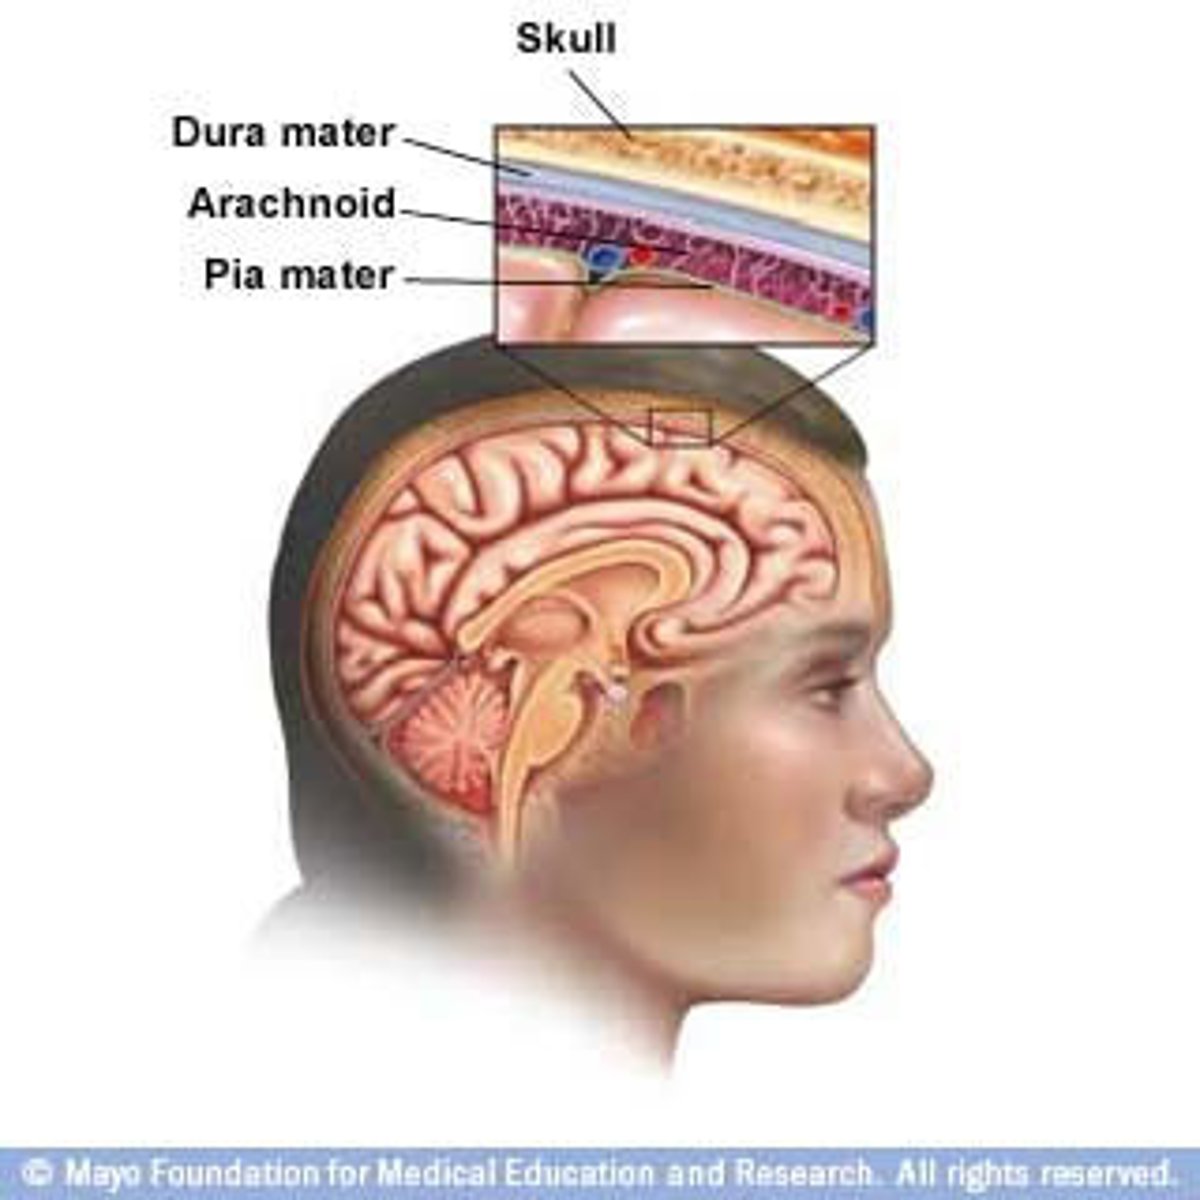

meninges function

protect brain and spinal cord

pia mater

deepest meninge, follows every contour of the brain

arachnoid mater

middle meninge, collagen and elastin fiber, spider web look

dura mater

made up of tough fibrous connective tissue, made up of the periosteal layer (creates periosteum of skull bone)

subarachnoid space

filled with cerebrospinal fluid